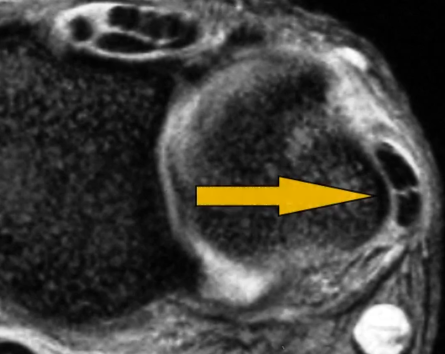

Déchirure Partielle

Déchirure Complète